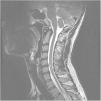

Posttraumatic syringomyelia (PTS) is a well-reported phenomenon that usually takes place in the long-term course of patients following spinal cord injury. Different surgical procedures have been described: spinal cordectomy is usually a last option technique, but might be an excellent choice in patients with severe spinal cord injuries.

We present a young patient with complete spinal cord injury after spine trauma, who developed posttraumatic syringomyelia with progressive motor deterioration twelve years after fixation. We performed a novel surgical technique (myelopexy) with excellent resolution of syringomyelia, sparing the negative implications of complete cord transection. Some artistic illustrations made by one of the corresponding authors are included, to better understanding of operative details.